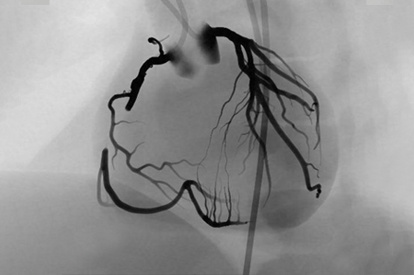

The ANGIO Mentor simulator is an essential tool for clinicians to practice and acquire the skills needed for performing endovascular interventions. Trusted by medical associations, hospitals, training centers, and the medical device industry globally, it provides trainees with realistic clinical settings to practice endovascular interventions using fluoroscopic and ultrasound guidance.

Offers true-to-life simulation of the clinical environment, including advanced imaging modalities like fluoroscopy/echocardiography, hemodynamic monitoring, medications, and interventional devices

Carotid Intervention Module

Cerebral Intervention Module

Transradial Cerebral Module

Acute Ischemic Stroke Module